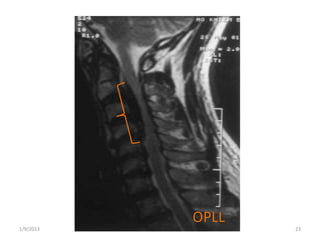

• Pathogenesis…

– OPLL (Ossification of Posterior Ligament)

• Preferential accumulation of calcium in posterior

ligament

• Common in Asian population

1/9/2013 23

OPLL